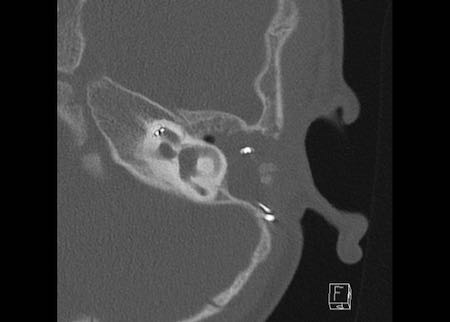

Bên trái là hình ảnh của một bé gái 2 tuổi.

Các hình ảnh từ kết quả chụp CT được thực hiện trước khi cấy ốc tai điện tử.

Quan sát thấy dị dạng nhẹ ở đỉnh ốc tai – không có sự phân tách giữa vòng thứ hai và vòng thứ ba, và trụ ốc tai xương vắng mặt.

Cống tiền đình bình thường.